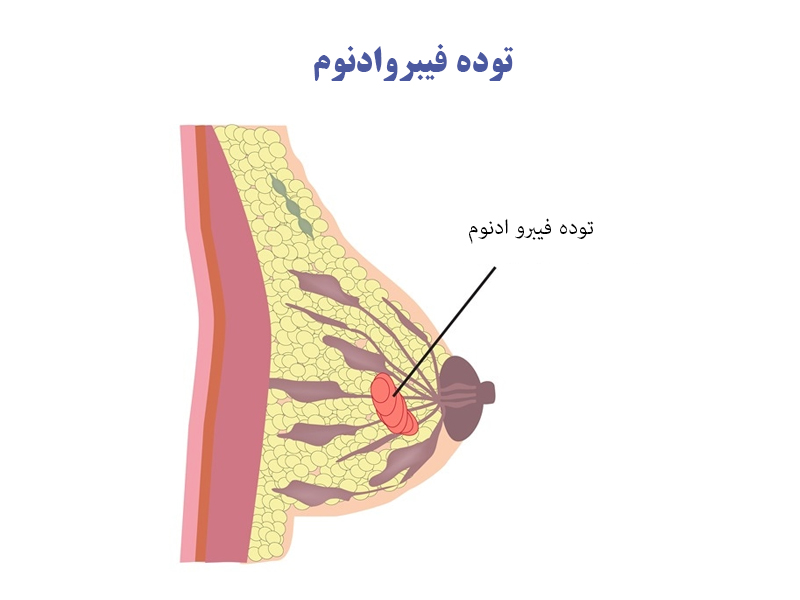

پیش از هر چیزی باید بدانید این نوع توده های فیبرواندومی نوعی از توده های خوش خیمی هستند که ممکن است بنا به دلایل مختلفی در سینه خانم ها ایجاد شوند. بر اساس یافته های انجمن جراحان سینه آمریکا تقریبا 10 درصد از زنان جوان آمریکایی پیش از ورود به 30 سالگی تشخیصی مبنی بر وجود توده فیبرواندوم در سینه هایشان دریافت کرده اند در این میان زنان آمریکایی و افریقایی بیش از سایر افراد رد معرض خطر ابتلا به این عارضه هستند. به طور خلاصه توده های فیبرواندوم از شایع ترین توده های غیر سرطانی در پستان ها است که با رشد بیش از حد بافت فیبری و غدد لنفاوی ایجاد می شود. این توده ها می توانند به طور همزمان در هر دو سینه ها یا یکی از آن ها رشد کند. ذکر یک نکته الزامیست این توده برخلاف توده های معمولی پستان که درون آن با مایعات پر شده است، درون این توده ها سلول وجود دارد که اصطلاحاٌ به آن solid mass هم می گویند.

توده فیبروادنوم چه علائمی دارد؟

از مشخصات وجود این توده ها در سینه ی خانم می توان به موارد زیر اشاره کرد:

- قابلیت لمس و حرکت توده ها در زیر دست

- معمولاٌ شکل گردی دارند.

- بافت نرم و لاستیکی دارند.

- از مهم ترین علائم ناشناخته این است که با وجود این توده معمولاٌ هیچ دردی را احساس نمی کنید اما ممکن است در برخی از افراد در هنگام لمس آن درد یا حساسیتی بروز پیدا کند.

- اندازه ی این توده ها اغلب از 2 سانتی متر هم کمتر است اما می تواند بیش از 10 سانتی متر هم رشد کند که در این صورت از آن ها تحت عنوان فیبرواندوم های غول آسا یاد می کنند. البته توجه داشته باشید که احتمال رشد این توده ها در دراز مدت وجود دارد.